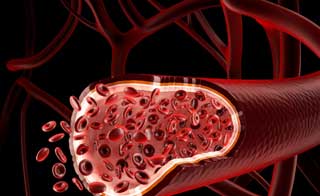

Ангиопротекторы представляют собой медикаменты, используемые в лечении сердечно-сосудистых заболеваний, и часто применяются в сочетании с корректорами микроциркуляции.

Эти препараты считаются незаменимыми при проблемах с оттоком и притоком крови в мелких сосудах, а также при снижении тонуса сосудистых стенок и появлении отеков. Ангиопротекторы помогают улучшить кровообращение, расширяют сосудистые просветы, укрепляют стенки сосудов и восстанавливают обменные процессы.

Ангиопротекторы представляют собой группу препаратов, которые используются для улучшения микроциркуляции и защиты сосудов. Врачи отмечают, что их действие основано на способности укреплять стенки сосудов, улучшать кровообращение и снижать проницаемость капилляров. Это делает ангиопротекторы особенно полезными при лечении заболеваний, связанных с нарушением венозного кровообращения, таких как варикозное расширение вен и хроническая венозная недостаточность.

Механизм действия ангиопротекторов до сих пор остается недостаточно изученным. Однако известно, что активация кровообращения в мелких сосудах способствует улучшению состава крови. Это, в свою очередь, помогает устранить отеки, нормализовать обмен веществ и повысить тонус сосудов.